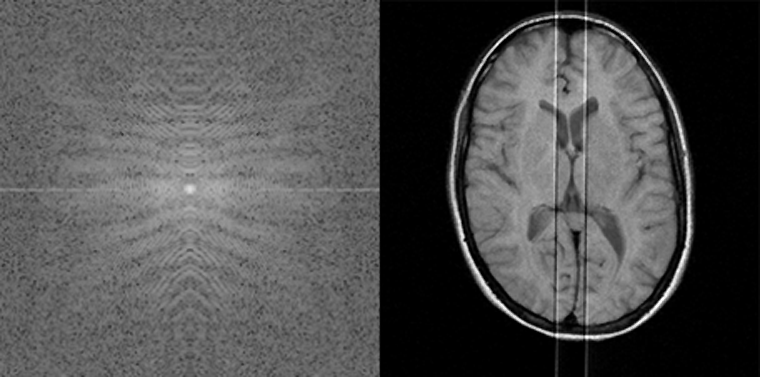

Figura 17-17:

k-Space artifacts: Aliasing or wrap-around artifact.

Figura 17-18:

k-Space artifacts: Radiofrequency feedthrough arti­fact.